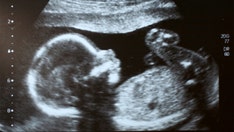

A Senate panel in Arizona approved on Thursday sweeping abortion legislation that would, among other things, prohibit the procedure from being performed based on an unborn child's Down syndrome diagnosis or other genetic abnormality.

Republican Sen. Nancy Barto of Phoenix said her proposal protects the most vulnerable and restores dignity to aborted fetuses by requiring that they be buried or cremated. Part of the legislation grants, in the case of surgical abortions, mothers the right to determine "the method and location for final disposition of bodily remains," according to the fact sheet. It also contained restrictions on medication abortions.